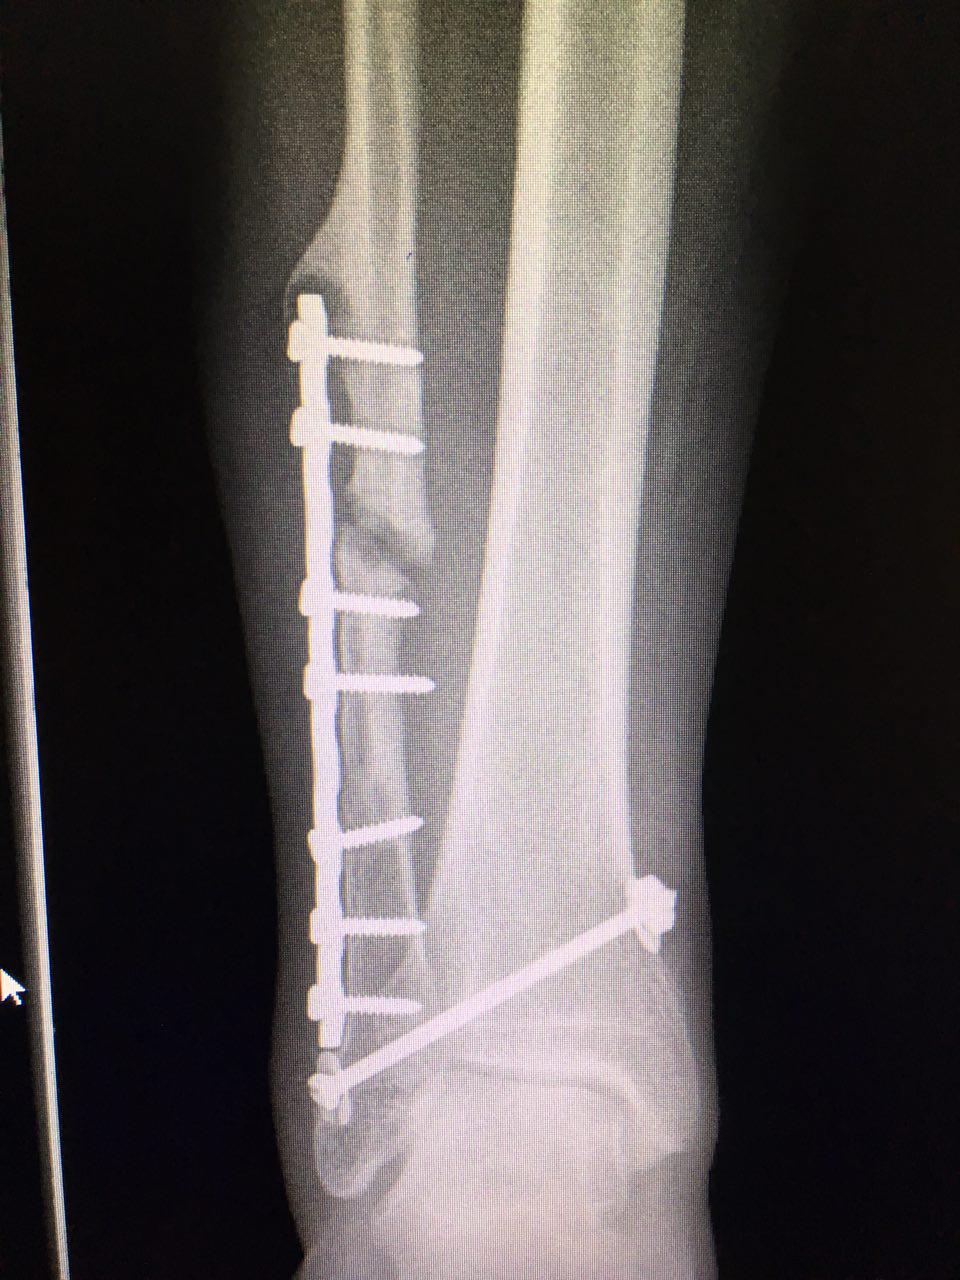

Хочу вернуться в спорт - Помогут ли пептиды?